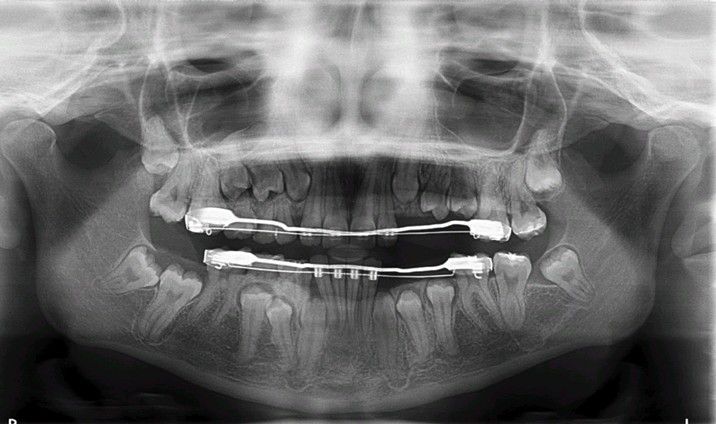

Delayed eruption

Adult patient presenting with multiple unerupted permanent teeth without obvious causation.